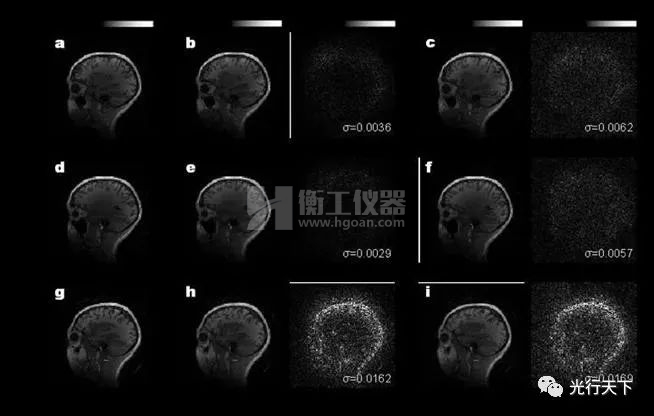

光學(xué)相干點(diǎn)積核芯片重構(gòu)結(jié)果與計算機(jī)結(jié)果的對比

本研究中,鄒衛(wèi)文教授團(tuán)隊利用醫(yī)學(xué)圖像重構(gòu)任務(wù)作為驗證,在芯片上成功地運(yùn)行了AUTOMAP(用于通用圖像重構(gòu))神經(jīng)網(wǎng)絡(luò)模型,圖像重構(gòu)的質(zhì)量接近了32位計算機(jī)的理想水平。該工作不僅推動光學(xué)神經(jīng)網(wǎng)絡(luò)研究領(lǐng)域攻克實際應(yīng)用難題,更為下一代智能計算技術(shù)提供了新思路。后續(xù)進(jìn)一步提高芯片的器件集成規(guī)模,有望實現(xiàn)更高速、更低功耗的光學(xué)神經(jīng)網(wǎng)絡(luò)處理器,緩解智能算力需求劇增與傳統(tǒng)硬件算力受限的矛盾。 該工作由上海交通大學(xué)、北京大學(xué)與中科院半導(dǎo)體所合作完成。上海交通大學(xué)為第一完成單位,博士研究生徐紹夫為第一作者,鄒衛(wèi)文教授為通訊作者。